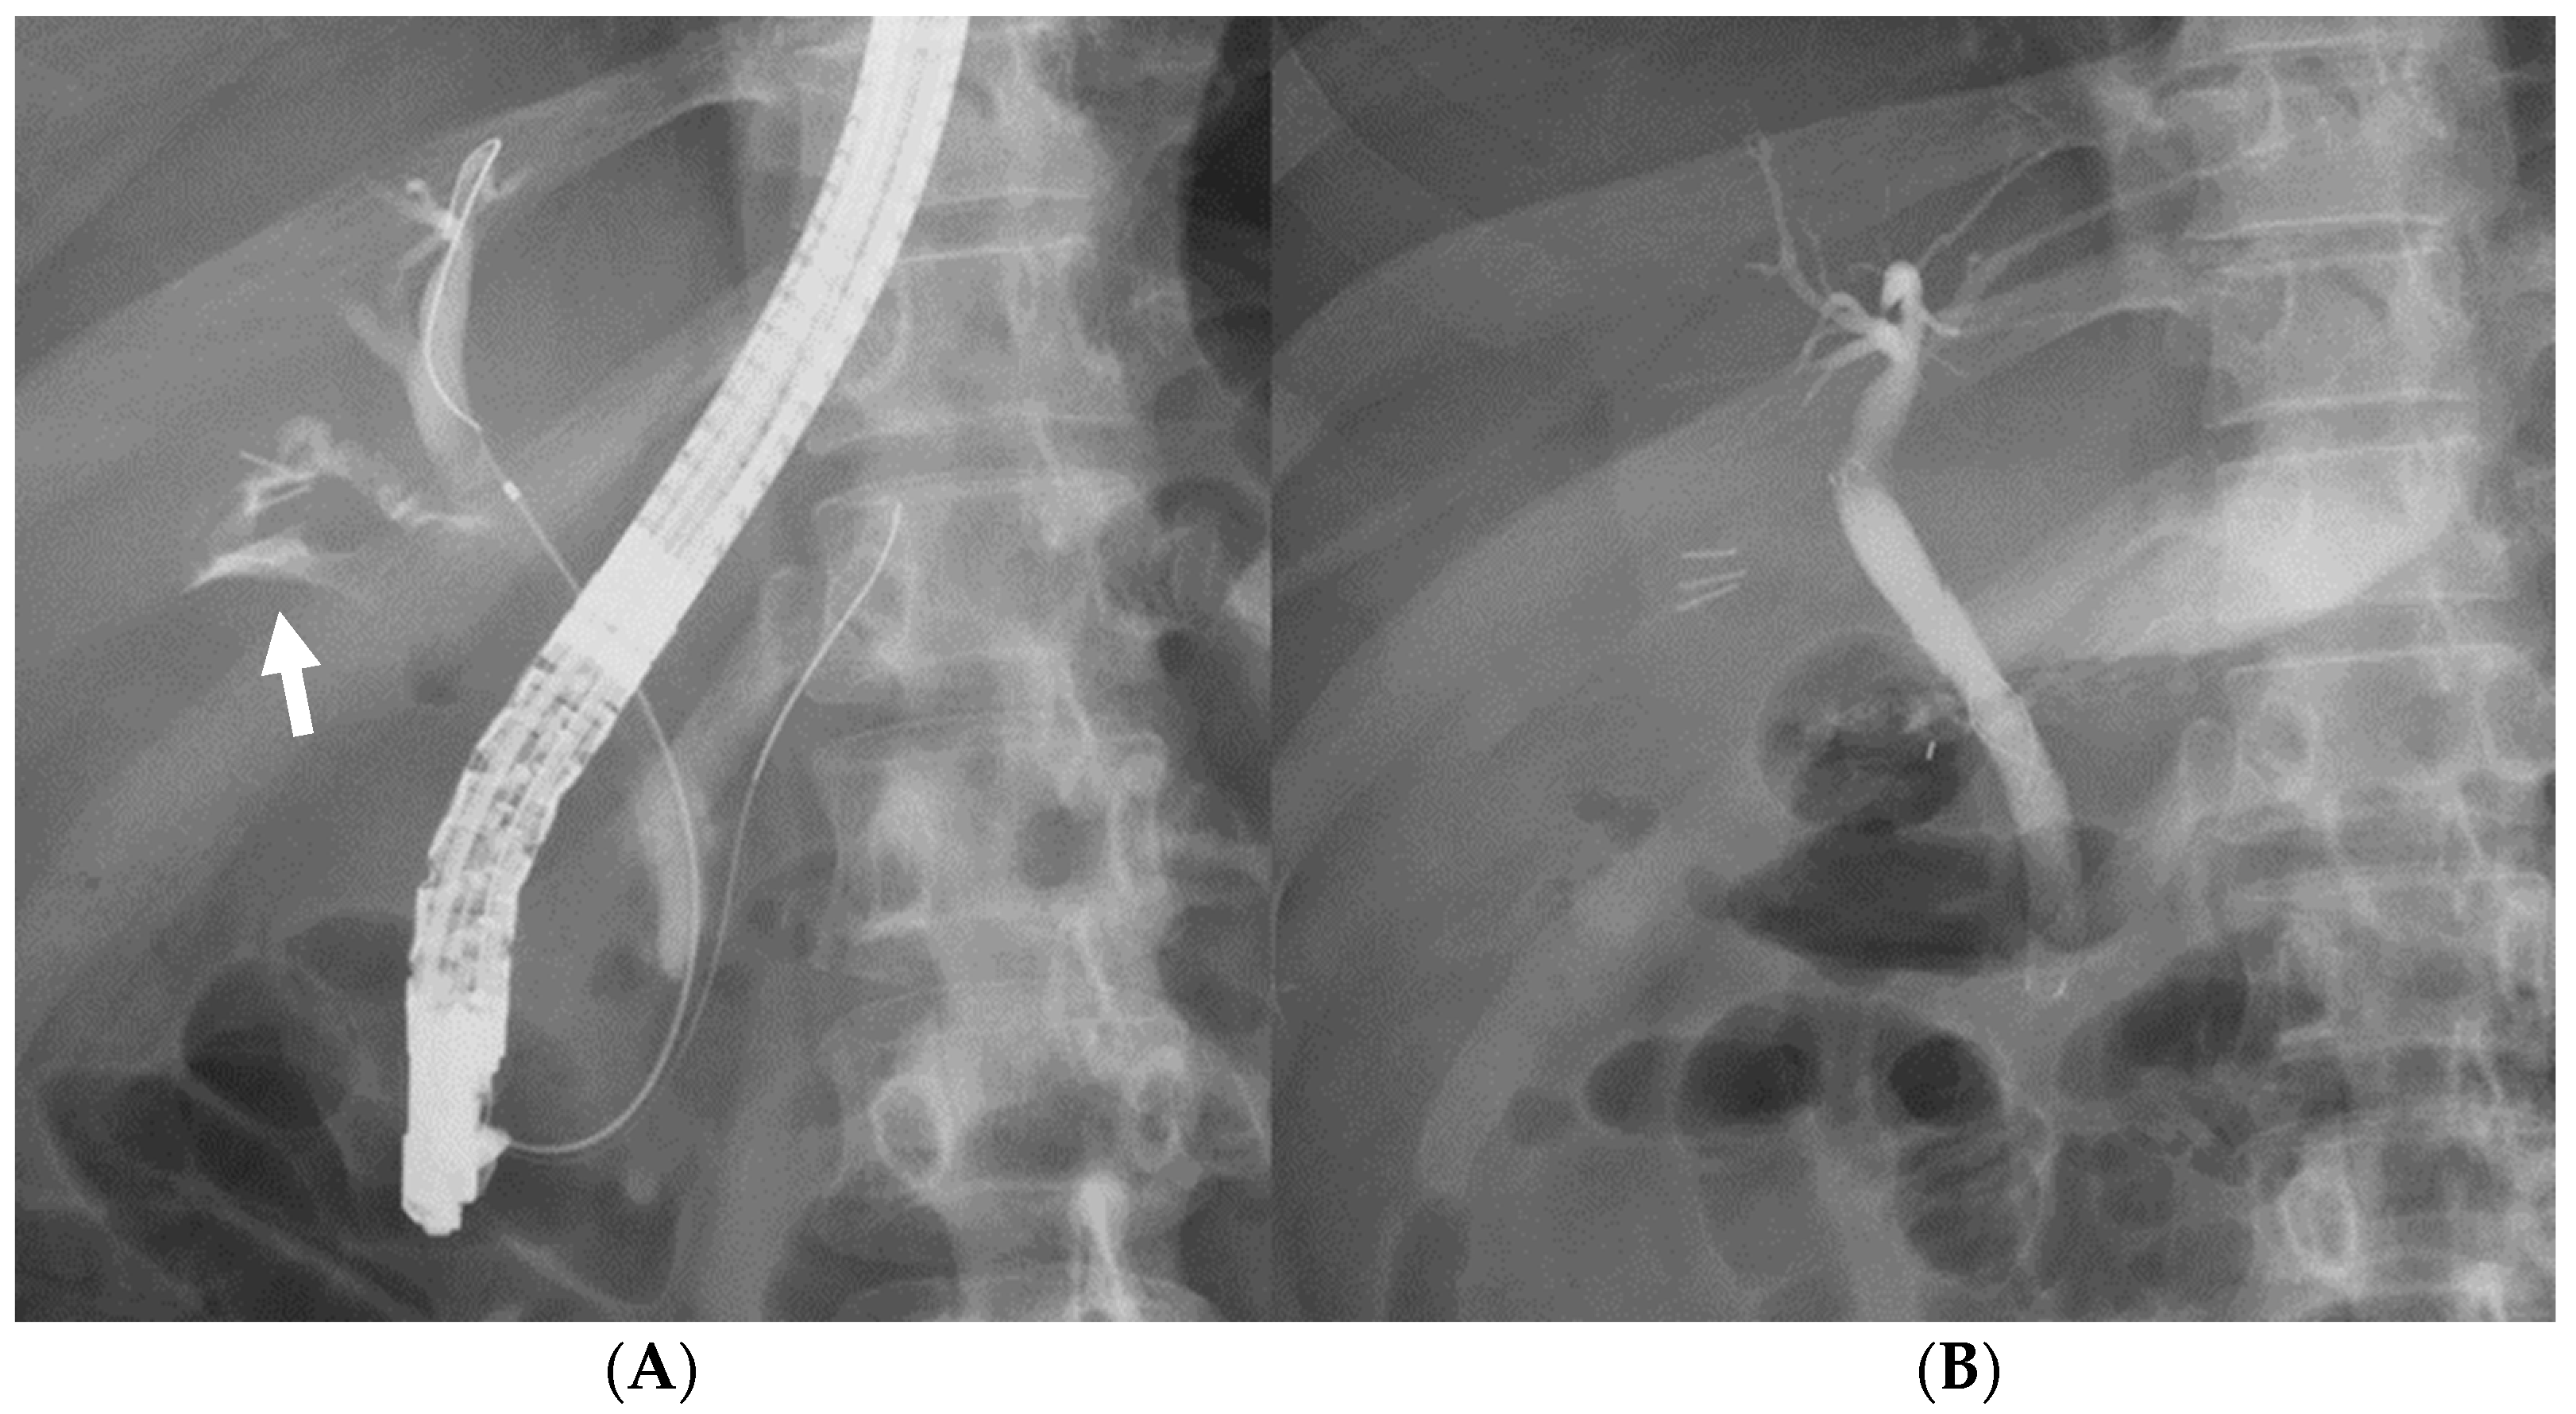

- Fukuda, K.; Nakai, Y.; Mizuno, S.; Sato, T.; Noguchi, K.; Kanai, S.; Suzuki, T.; Hakuta, R.; Ishigaki, K.; Saito, K.; et al. Endoscopic Bridge-and-Seal of Bile Leaks Using a Fully Covered Self-Expandable Metallic Stent above the Papilla. J. Clin. Med. 2022, 11, 6019. [Google Scholar] [CrossRef]